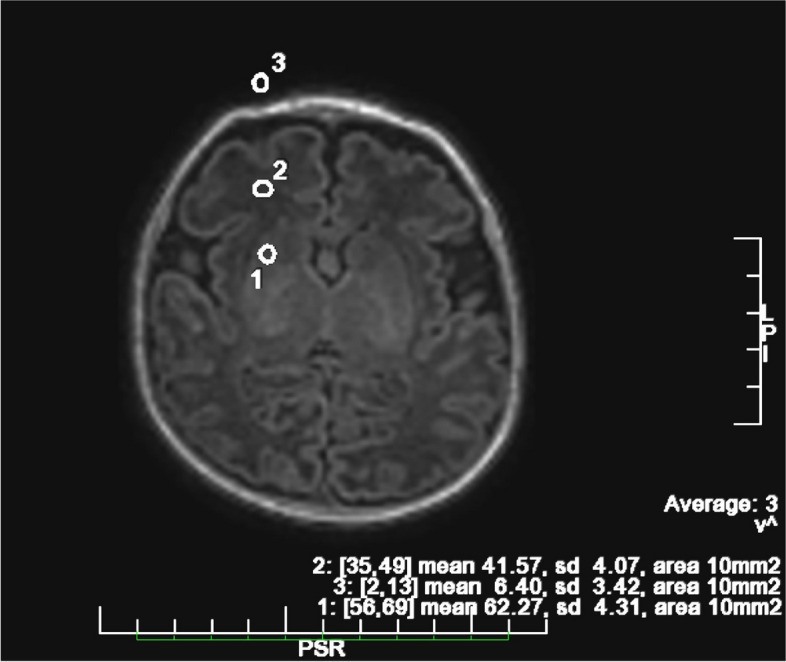

Results: We enrolled 23 consecutive preterm babies born < 37 weeks gestational age, candidates for sedation for elective brain magnetic resonance imaging. All patients completed the radiological procedure in 30 min (SD ± 6.39 min) without complications requiring exam interruption. Only one patient (4%) experienced a transient desaturation, while 2 neonates (9%) showed apnea lasting > 20 s. On average, there was a 1 °C decrease in body temperature and full enteral feeding was resumed within 1.5 h. Neuroradiologists rated the quality of the images obtained as high.